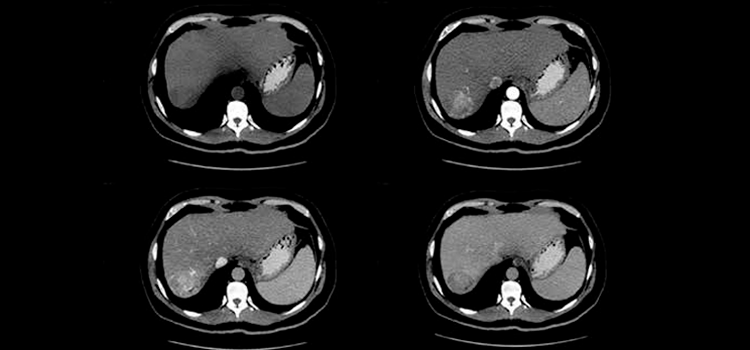

Este estudio pionero revela mecanismos moleculares previamente no descubiertos que son fundamentales en la progresión del tejido hepático sano al carcinoma hepatocelular (CHC), la forma más común de cáncer primario de hígado

El CHC se caracteriza por su alta heterogeneidad y complejidad. Los tratamientos actuales, basados en terapias sistémicas de primera y segunda línea, han propiciado un incremento en la supervivencia de los pacientes, sin alcanzar, sin embargo, los resultados positivos vistos en otras neoplasias. Por consiguiente, este trabajo propone estrategias terapéuticas combinadas y la identificación de nuevos blancos terapéuticos en CHC, resaltando la capacidad terapéutica de la SUMOilación y su influencia en procesos nucleares críticos como la transcripción, la respuesta al daño del ADN y el ciclo celular.